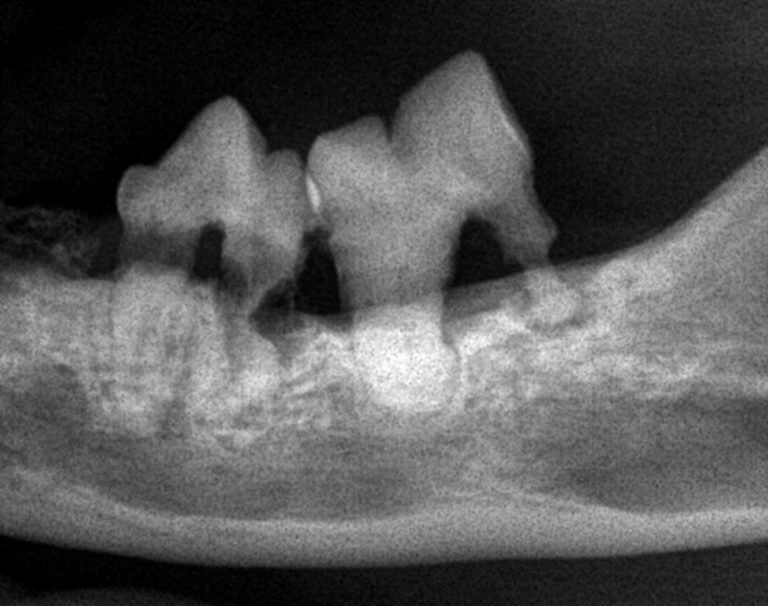

見た目では歯がしっかりしているように見えても、歯科用レントゲンを撮ると歯が根元から溶けていることがはっきり分かります。

吸収病巣(FORL:Feline Odontoclastic Resorptive Lesions)は、歯の表面や根の部分が少しずつ溶けていってしまう病気です。

外からは分かりにくいため、レントゲン検査で初めて診断できるケースが多いのが特徴です。